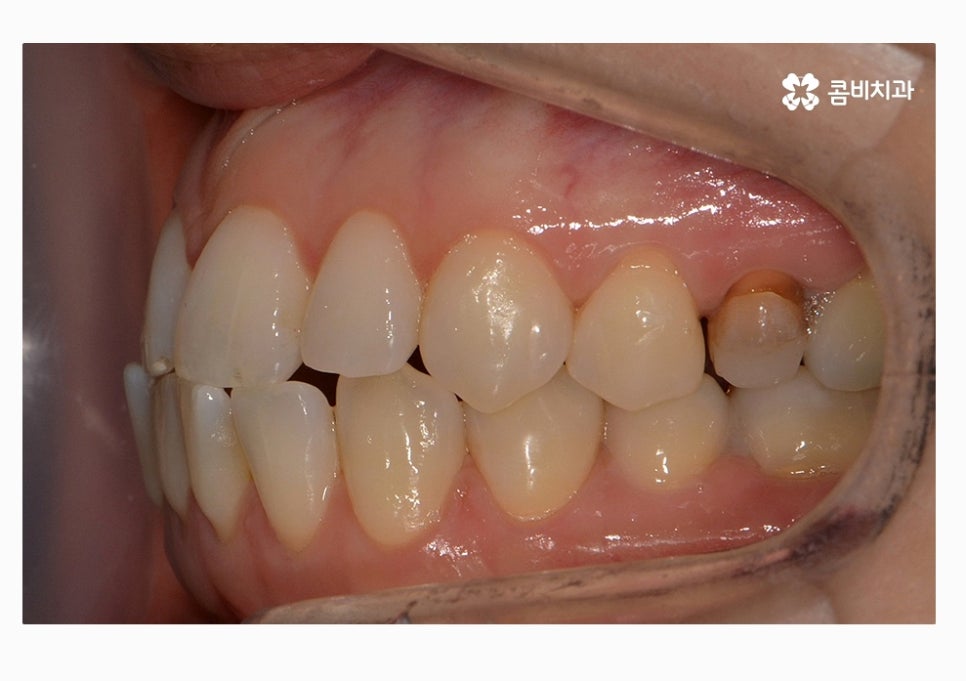

부정교합의 종류도 다양하지만 오늘 보시는 케이스의 경우

절단교합 + 3급부정교합에 해당하며 아랫니가 과하게 앞으로

돌출된 경우에는 치열뿐 아니라 주걱턱과 같이

얼굴형에도 영향을 줄 수 있어요.

치열 사진을 볼 때 정면보다는 옆모습으로 볼 때

아래 어금니가 위 어금니보다 앞으로 나와있고

앞니 교합이 제대로 맞물리지 않는다는 것이 눈에 띄게 나타나는데